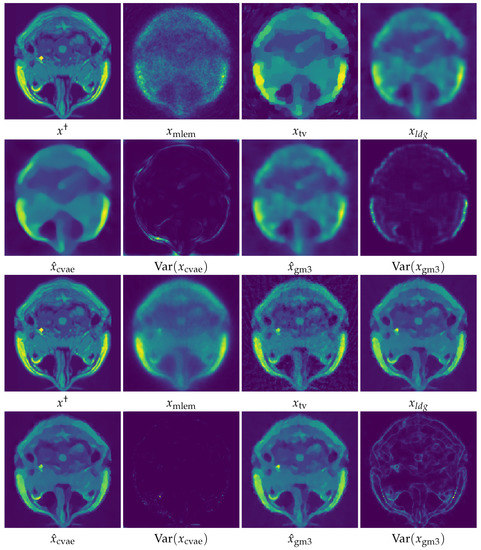

5. Numerical Experiments and Discussions